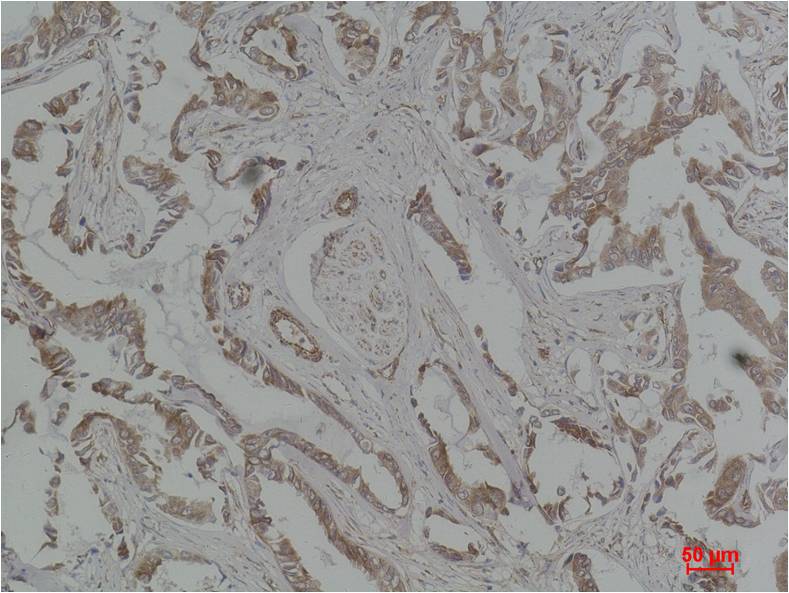

| Dilutions: | WB 1:1,000-2,000 IHC 1:200-500 |